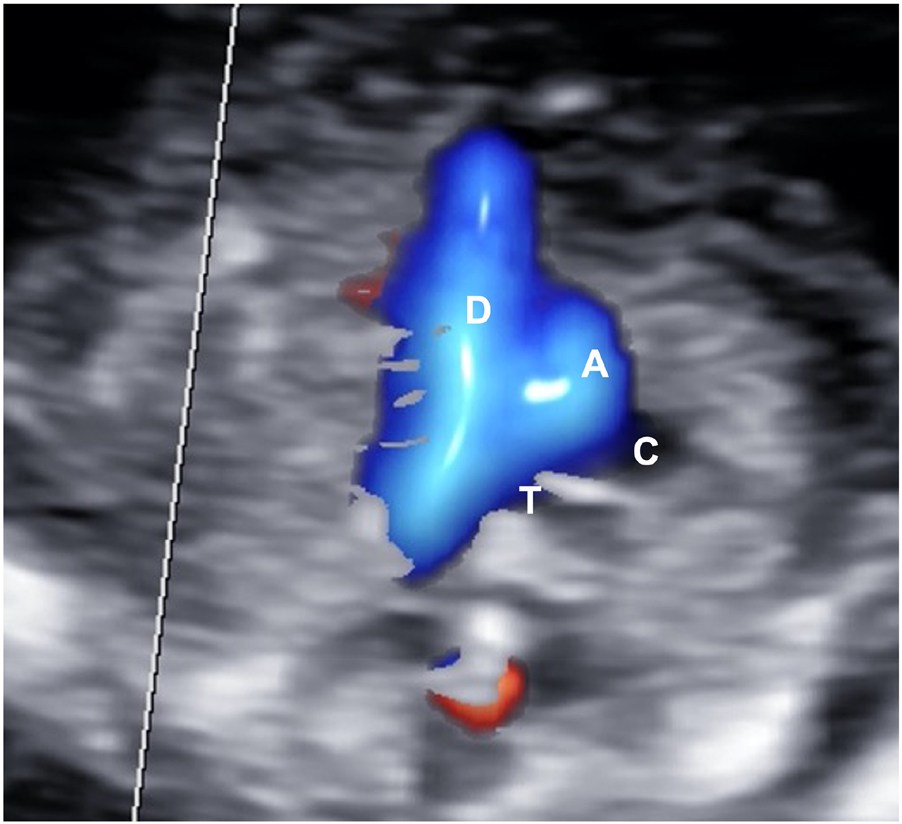

The fetal heart lies in the middle of the fetal chest, occupying about one third of it, with the apex pointing towards the left side and with two thirds of its area on the left of the thoracic midline. The four chambers should be balanced in size, with the ventricles mildly bigger than the atria (Figure 6). The great arteries are similar in size but showing opposite direction (crossover of the outflow tracts). The aorta arises from the left ventricle and points to the right and the pulmonary artery from the right ventricle but with an anteroposterior direction, roughly parallel to the midline. The aortic and ductal arches could be visualized just above the outflow tracts joining just before and to the left of the fetal spine (Figure 7). At the same level, the superior vena cava could be possibly visualized in the context of a “3 vessel and trachea” view.

Aortic (A) and ductal (D) arches (V-shape) highlighted by color Doppler on a three vessels and trachea view.

The aortic arch is on the left of the trachea (T). Superior vena cava (C) is just on the right of the aorta (A).

The visualization of the three-vessels or arches view (V-sign) on the axial plane by color Doppler is suggested but not mandatory in the first trimester.

The plane, including the arches, could be obtained starting from the four chambers apical view, sweeping the probe cranially. Such structures could be highlighted by color Doppler, which would appear similar in size and color in normal conditions.